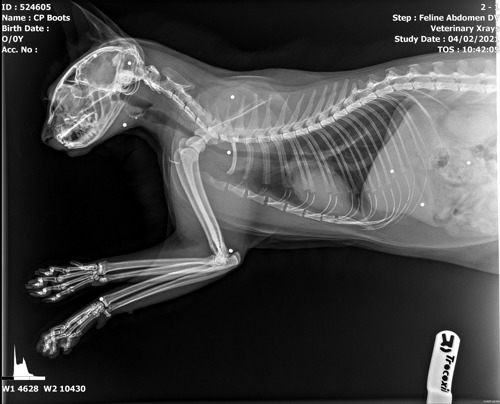

A cat care assistant spotted a lump beneath one of her ears. It was only after x-rays were taken that the full extent of Boots’ injuries were revealed.

Centre Manager Sue Dobbs explains: “We thought the lump near Boots’ ear was going to be a foreign object because of its size and shape but it wasn’t until our vet removed it and I examined it that I realised it was pellet. A further scan then revealed her numerous injuries.

“It really is a miracle Boots survived the shooting. We can see from the x-rays that the pellets narrowly missed vital organs, her spinal cord and her brain.”

x-ray of a cat showing shotgun pellets lodged in bodyBoots' x-ray showing some of the pellets lodged in her body. Credit: Shepherds the Vets

The vets managed to remove nine of the pellets but five were deemed too dangerous to take out.

Veterinary Surgeon Katrina Cordell said: “They were everywhere – behind her ear, under her chin, and even in her tail. Any one of them could have been fatal. We’re confident the remaining pellets won’t cause her problems. She is a very lucky kitty at the end of the day, none the worse for wear other than a rather odd looking haircut and a few stitches.”